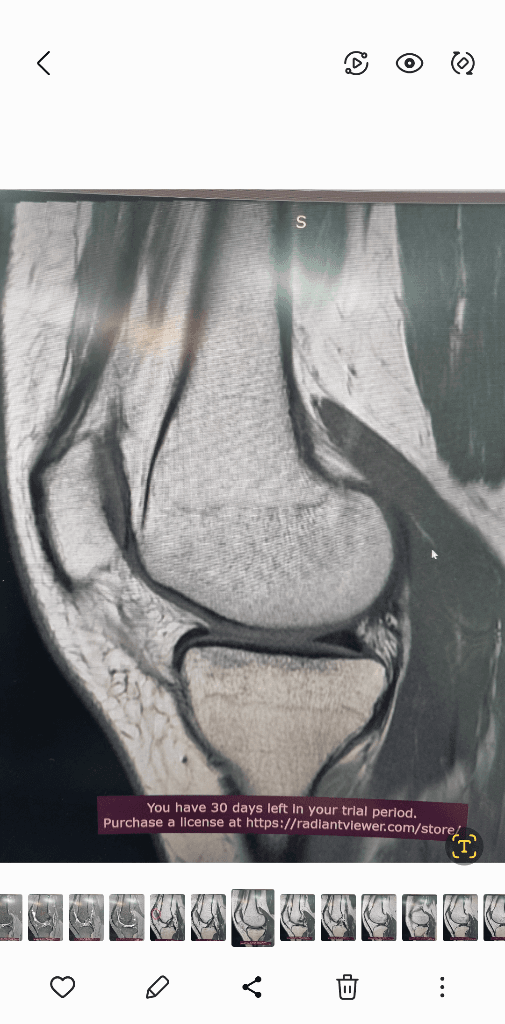

1. 추벽이 아닙니다.

2. 슬개골 관절면에 외상으로 인한 골수부종입니다.

3. 관절면 손상여부는 첨부해주신 영상만으로 알 수 없습니다